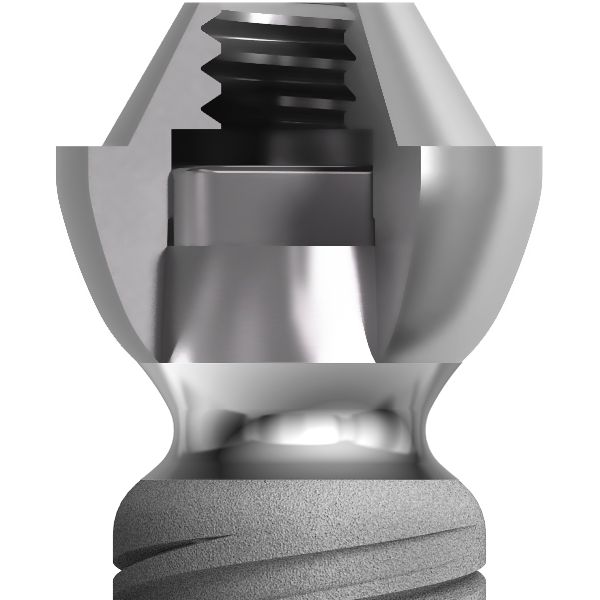

Cette technique requiert avant tout une bonne stabilité primaire des implants puis une contention à la fois fixe, rigide et passive des implants entre eux grâce à une prothèse transitoire qui jouera le rôle de fixateur externe.